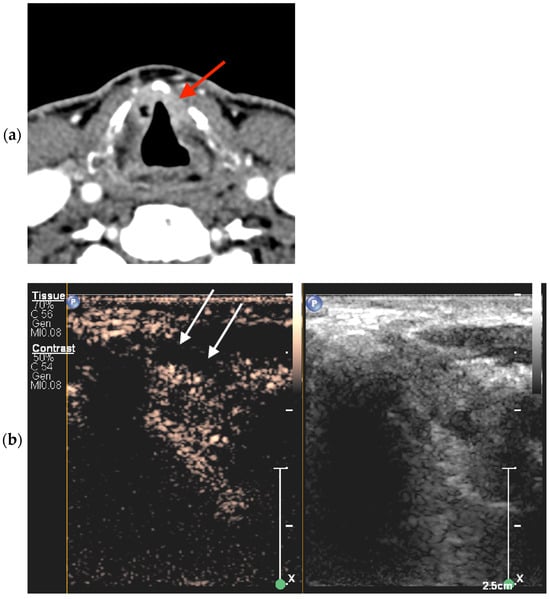

2.5.1. CEUS Imaging

2.5.2. Cross-Sectional Imaging